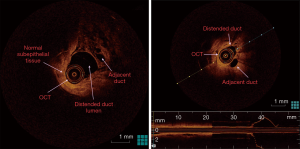

The fluid-yielding duct of the prophylactic mastectomy specimen was scanned with OCT in order to obtain abnormal imaging. Cross-sectional OCT images acquired from the ductal lining showed normal (sub-)epithelial layers proximally and round undefined lesion adjacent to the distended duct distally (Figures 2,3). Ductoscopy failed to show the lesion acquired by OCT. The lesion was 2.5 cm away from the nipple with a diameter of 1 mm, which was measured during OCT scanning. The histopathology revealed a florid ductal hyperplasia (FDH), which causes obliteration in the ductal lumen (Figure 3). This is the first time in the literature an OCT imaging of an FDH in a breast duct was acquired endoscopically or intraductally. The impact of this imaging case was the unique discovery of a high-risk lesion by intraductal OCT, which could not be detected by any conventional imaging.

To our knowledge, no study has been published in the literature regarding real-time cross-sectional imaging of ductal space by OCT, which enters via nipple orifices. Since the milking ducts are very narrow to enter, only mini-endoscopic instruments such as ductoscopy have been developed to acquire images of pathologic lesions (7). OCT studies on breast include only the analysis of OCT to evaluate surgical margins of lumpectomy specimens (8,9). Furthermore, the OCTs used in those studies did not include a catheter aid to acquire cross-sectional images via natural orifice. However, we used a catheter-based OCT to enter the natural duct orifices in order to achieve direct images from epithelium and layers underneath. Intraductal OCT were able to show ductal epithelium, layers and cavities as cross-sectional images similar to standard hematoxylin & eosin slides. The distention of the duct by saline made the OCT procedure more efficient than the use of the catheter in shrunken ex vivo ducts. The distention did not upgrade resolution, however, made the images of the ductal epithelial layer, lumen, and lesion more clear and distinguishable than the images acquired in shrunken ducts. The use of OCT catheter in vivo in future studies would also need saline infusion and distention from our experience on ductoscopy used for PND which is very similar technically (2-4).

Recently, Yemul et al. (13) assessed mastectomy and breast-conserving surgery specimens from 26 women who were imaged with a handheld OCT probe. Histology slides corresponding to the OCT image region were digitally photographed. OCT and histology images from the same region were paired by selecting the best structural matches. In total, 2,880 OCT images were acquired from 26 breast specimens, and 48 matching OCT-histology image pairs were identified. Differentiation between pathologies was achieved by considering feature boundaries, interior appearance, posterior shadowing or enhancement, and overall morphologic patterns. The results indicate that OCT can be used to identify and distinguish between benign and malignant features in human breast tissue. In our study, round lesion approximately 1mm with a border were found, which caused complete obstruction in the duct shown as hyporeflective interiors and well-circumscribed boundary architecture with distinct edges. These architectural findings of FDH in our study are similar to the findings of Yemul et al. as a hyporeflective interior, less distinct boundaries for hyperplastic ducts.